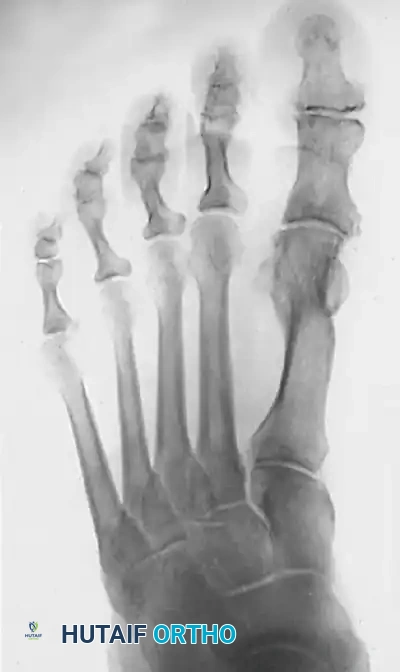

Image

Figure 3: Standing AP radiograph 1 year postoperatively. The patient underwent a chevron osteotomy, release of the adductor hallucis, an Akin osteotomy of the proximal phalanx, and correction of the second hammer toe. Note the excellent consolidation of the osteotomy, restoration of the IMA, and congruent first MTP joint.